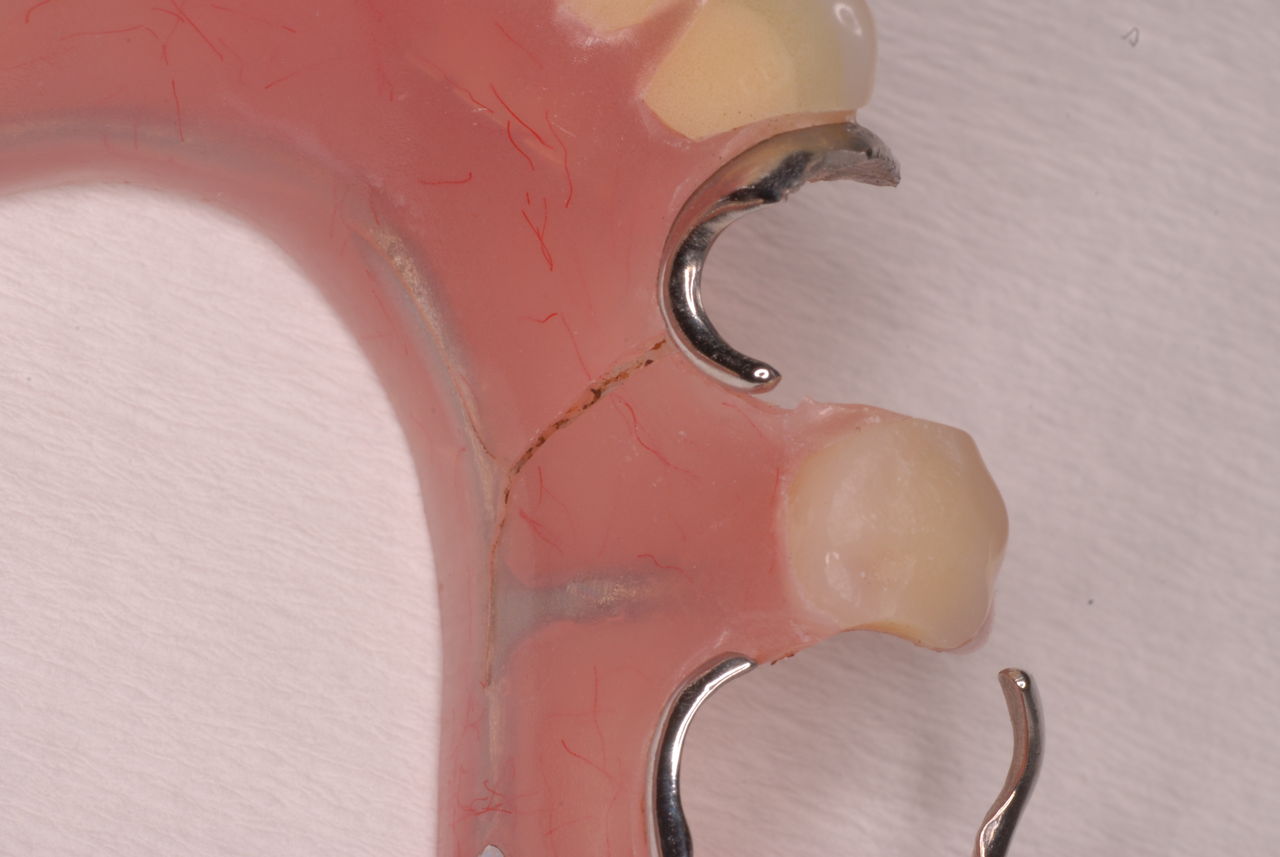

クラスプという歯を取り囲むワイヤ−が折れたりしてまともに機能していません。構造的な問題もあるのでしょうがヒビも目立ちます。殆ど使わずに御蔵入りとなったようです。値段の問題からかそうではないか判然としませんが、入れ歯というのは残りの歯や歯周病の治療がある程度完了してからでないと良い機能的な入れ歯などはできません。せいぜい治療中用の簡素な物を作成して歯や歯茎の病気が治るのを待ちながら様子をみるしかないのです。